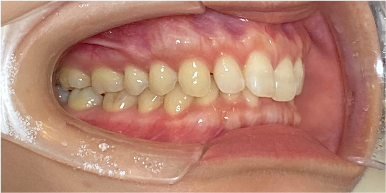

34歳女性のビフォーアフター

| 診断 | 叢生(デコボコがある状態)、開咬、下顎前突 |

|---|---|

| 治療方針 | インビザラインシステムにて主にIPR(歯と歯の間をわずかに削合してスペースを獲得する方法)を組み込んだ動的矯正治療を行った叢生改善と、開咬の改善のため臼歯部圧下をメインとした動的治療を行い、保定を行う。 |

| 治療費 ※ | 99万7千円(診断、型取り、PMTC、保定装置を含む料金) |

| 治療期間 | 3年5か月 |

| リスク | 1日20時間以上マウスピースを使用できない場合、歯が動かない可能性がある。装着時や食事時に痛みを伴う。歯肉退縮や虫歯になるおそれがある。また、指導通りに装着できていない場合や適切なブラッシングが出来ていないとそのリスクが高くなる。歯根が短くなることがある。ごくまれに歯の神経が損傷してしまうことがある。過去にぶつけたり深い虫歯治療をしたことがあるとそのリスクはやや高くなる。矯正後には保定装置が必要。適切な使用ができない場合、後戻りの原因となる。将来的に歯並びが動いて再矯正が必要な場合がある。舌癖が強い場合や正常に生えていない親知らずがある場合、その可能性が高くなる。 |

※ 治療費は、治療当時の費用で、現在の費用と異なる可能性があります。現在の費用は治療費のページでご確認くださいませ。